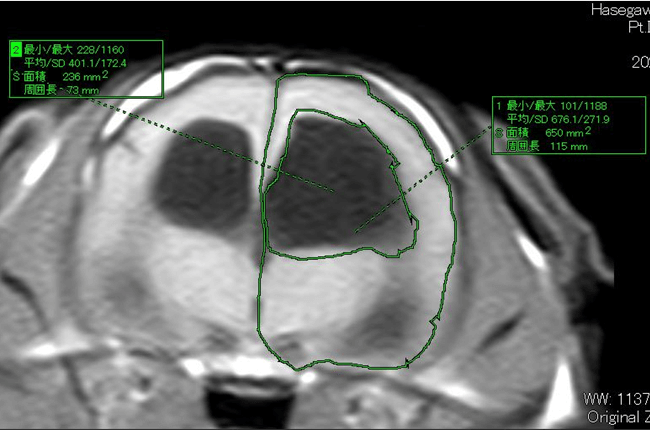

◈ 水頭症

MR画像(T2WI)

MR画像(T2WI)